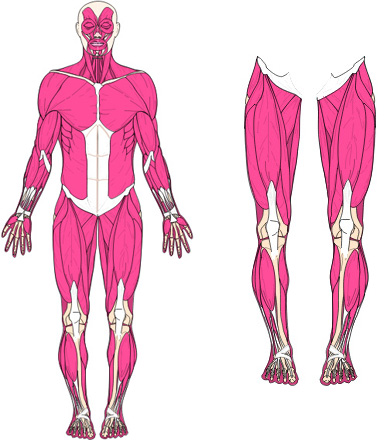

Die Muskeln benötigen die Knochen-Hebel als Kraft-Übersetzung.

Befindet sich Spannung und Gegenspannung nicht im Gleichgewicht, verzieht es das Skelett. Dadurch verändern sich Knochen- und Gelenkstellungen, was zu einseitiger Überbelastung führt und vielmals als Arthrose betrachtet wird.

Diese Fehl-Spannungslinien verursachen Überdehnungsschmerzen, Durchblutungs- und Lymphsystem-Störungen. Die Spannungslinien führen auch zu inneren Blockaden von Organen, Organ-Verbindungen, die wiederum unterschiedliche Beschwerden verursachen können.

8. Das heisst: Für die Bewegung benötigt es die Muskelkraft. Für die Kraftoptimierung benötigen die Muskeln die Skelett-Knochen. Sind laut Statik die Kräfte im ruhenden Zustand nicht ausgeglichen, verformt des den Körper, indem es ihn komprimiert verzieht und verdreht. |

Im Wissen, das sich kein Skelett aus eigenem Antrieb bewegen kann. Für den Zusammenhalt der Knochen, Gelenke, Wirbelkörper und die Bewegung sind die Muskeln, Sehnen und Bänder verantwortlich.

Muskulatur / Sehnen und Bänder

Muskulatur, Sehnen und Bänder sind für die Bewegung und den Zusammenhalt des Skeletts verantwortlich. Die Muskeln benötigen die Knochen als Kraftübersetzung. (ein gesunder Mensch ca. 656 Muskeln)

Statik

Die Statik beschreibt unter anderem, dass die Kräfte im ruhenden Zustand ausgeglichen sein müssen, ansonsten verzieht, komprimiert oder verdreht es den Körper.

Hebelgesetz

Nach dem Hebelgesetz können z. B. mit 5Kg je nach Hebellänge 100 Kg im Gleichgewicht gehalten werden. Dadurch wird auch klar, wie Spannungsunterschiede das Skelett verziehen.

Diese Einseitigen Kräfte

Sind verantwortlich für die Ausweich- und Kompensations-Haltungen. Diese wiederum verändern Skelettstellungen über Knochen, Gelenke und Wirbelkörper.

Ursachen von Problemen am Skelett können in vielen Fällen nicht von diesem ausgehen. Tatsache ist: Das ohne Bänder, Sehnen und Muskeln das Skelett in sich zusammenfällt. Somit ist das Skelett mit seinen Knochen, Gelenken und Wirbelkörper elastisch.

Weil sich Muskel/Sehnen Ansätze zur optimalen Kraftübertragung häufig in Gelenk- und Wirbelnähe befinden, werden die Muskel / Sehnen Überdehnungen vielmals als Gelenk oder Rückenbeschwerden / Schmerzen wahrgenommen. Die Summe der Fehlspannungen und deren Ausweichhaltungen führen so automatisch zu Belastungs-, Durchblutungs- und Funktions-Störungen, die sowohl das Skelett, als auch die Muskulatur Linien und dadurch auch innere Organe und Organverbindungen betreffen können.